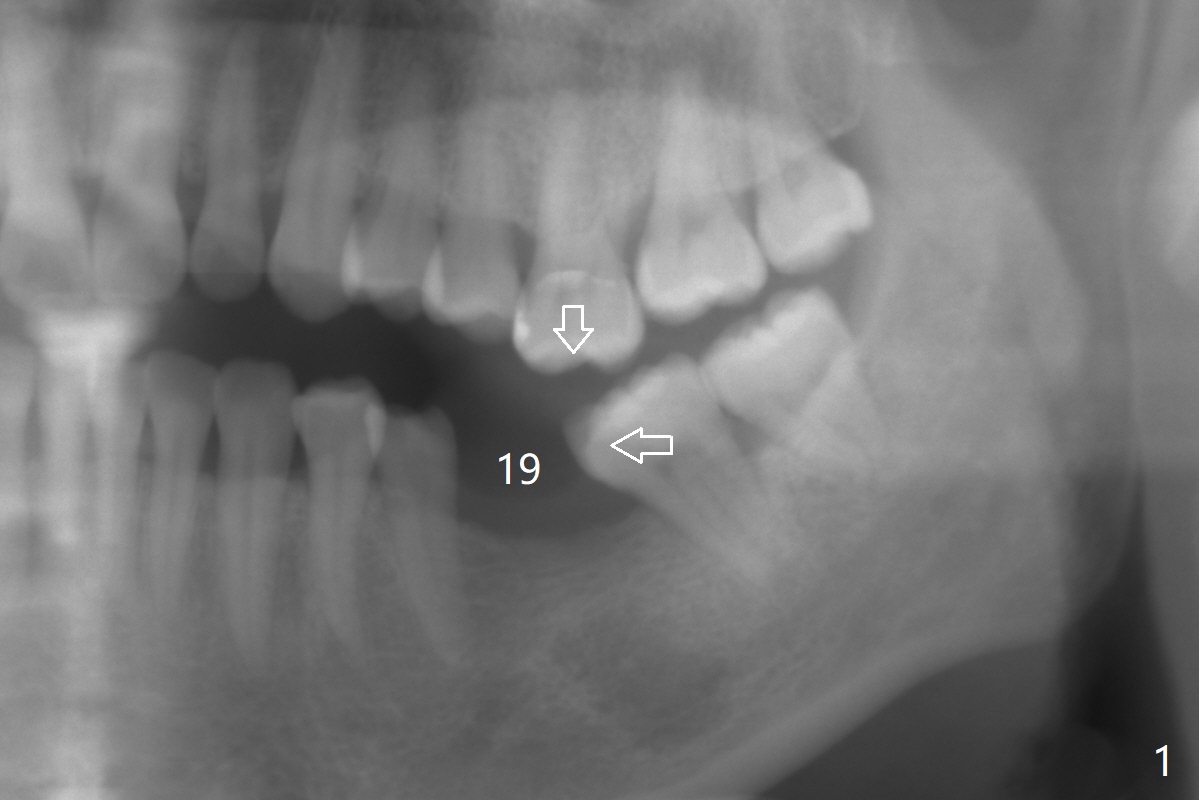

A 46-year-old woman has lost the tooth #19 since middle school with supraeruption of the tooth #14 and mesial tilt of the teeth #17 and 18 (Fig.1 arrows). After slightly distal placement of an implant at #19 with guided surgery (Fig.2), two minimplants will be placed for intrusion of the tooth #14. Upon implant osteointegration, a provisional will be fabricated with supraocclusion to facilitate the intrusion and upright the tooth #18 with extraction of the tooth #17. Fig.3 is a coronal section of CT of the roots of the tooth #14, showing 1.6x8 mm and 1.6x10 mm mini-implants to be placed mesiobuccal and distopalatal. A 5x8.5 mm implant will be placed at the site of #19 (Fig.4).